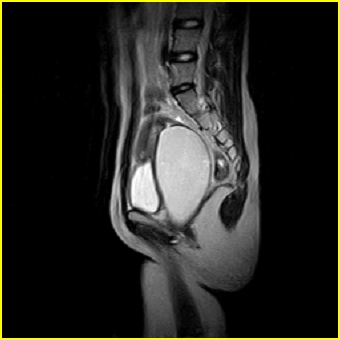

女、15岁、下腹疼痛2天,排尿困难1天。查体:处女膜闭锁,距处女膜约4至5cm处扪及一约5cm直径的圆形包块,张力较高,触痛明显、欠活动。b超提示子宫增大伴宫内增强回声团。

更正影像意见:阴道积血。

处女膜闭锁,阴道积血,子宫积血.

先天性处女膜闭锁,伴阴道积血,不除外先天性阴道粘液囊肿形成。

处女膜闭锁,伴子宫及阴道积血.